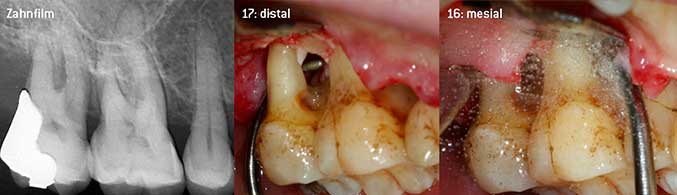

Offenes Debridement der Furkationen an 16 und 17

Abb. 3: Offenes Debridement der Furkationen an 16 und 17 bei fortgeschrittenem Attachmentverlust

Als Initiatoren zur Entwicklung der neuen diamantierten Luftscaler-Spitze 3AP sahen es beide Zahnärzte als notwendig an, die Einschränkung in der Handhabung bisher kommerziell vermarkteter diamantierter Spitzen insbesondere während der Furkationstherapie oder in engen Knochentaschen zu verbessern. Dies sollte unabhängig von nicht-chirurgischem (Abbildung 2) oder chirurgischem Vorgehen sein (Abbildung 3).